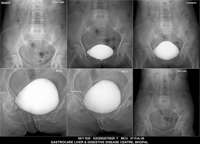

Section: URETHROGRAM Total: 95 images